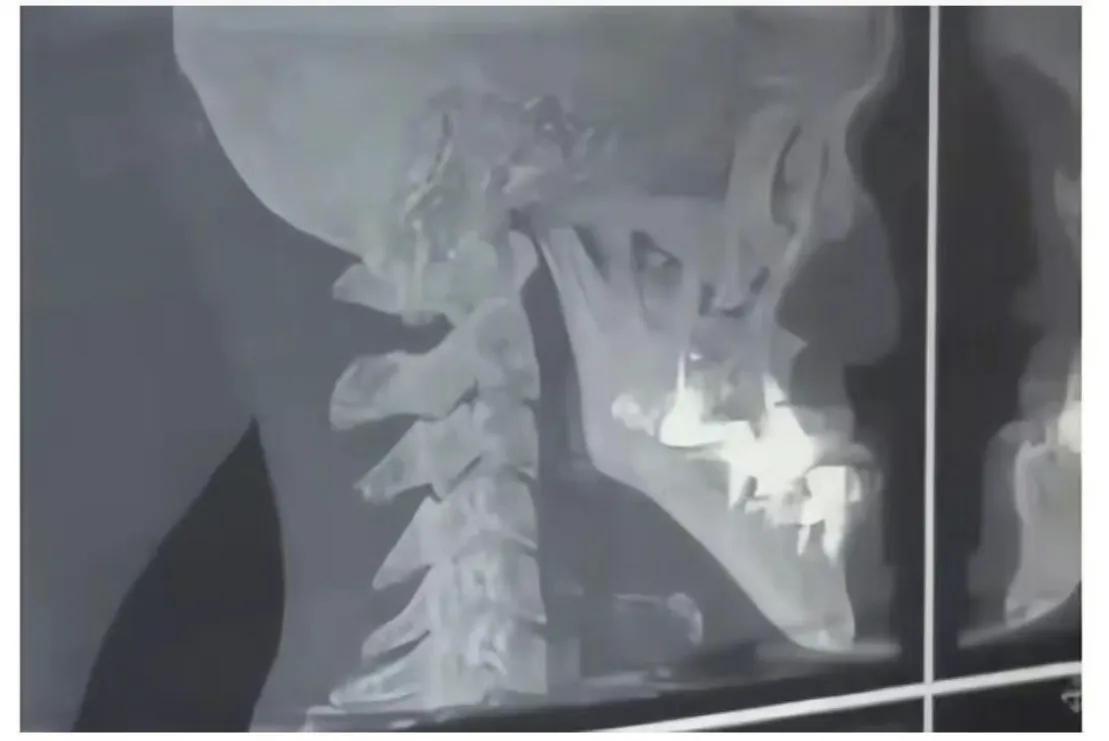

醫(yī)生又認為是牙齒和骨骼問題,結果拍片發(fā)現城之內一切正常,這就讓人百思不得其解了。

片子正常

城之內牙齒沒有問題,只是單純的下巴過長。